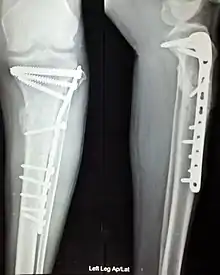

Internal fixation is an operation in orthopedics that involves the surgical implementation of implants for the purpose of repairing a bone, a concept that dates to the mid-nineteenth century and was made applicable for routine treatment in the mid-twentieth century.[1] An internal fixator may be made of stainless steel, titanium alloy,[2] or cobalt-chrome alloy.[3] or plastics.

Open Reduction Internal Fixation (ORIF) involves the implementation of implants to guide the healing process of a bone, as well as the open reduction, or setting, of the bone. Open reduction refers to open surgery to set bones, as is necessary for some fractures. Internal fixation refers to fixation of screws and/or plates, intramedullary rods and other devices to enable or facilitate healing. Rigid fixation prevents micro-motion across lines of fracture to enable healing and prevent infection, which happens when implants such as plates (e.g. dynamic compression plate) are used. ORIF techniques often are used in cases involving serious fractures such as comminuted or displaced fractures or, in cases where the bone otherwise would not heal correctly with casting or splinting alone.

Various techniques of minimally invasive surgery for internal fixation of bones have been reported. The treatment of fractures of the distal third of the tibia has evolved with the development of improved imaging and surgical techniques.[5]